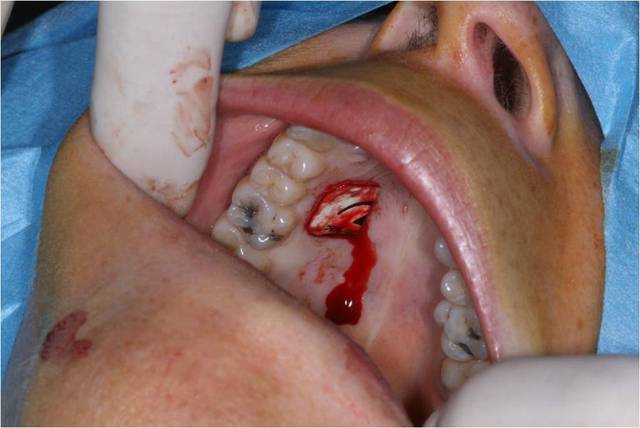

Bon bein voil c'est fait .

Préparer le lit reveveur ok

Le prelevement et la préparation du greffon c'est le plus facile

La ou j'ai eu le plus de difficulté c'est au moment de la mise en place du greffon. Meme en y mettant tout mon courage et ma volonté et du fils 5/0 j'ai pas reussi a suture le lambeau aux papilles . Conclusion il est descendu ... Sinon la freinectomie a pu etre fait sans probleme, lambeau bien plaqué et immobile .

Pour la cicatrisation je croise les doigts.

Impossible de suturer au papilles malgres tout mes efforts :/ . La greffe est legerement descendu

La 2ieme photos correspond au dessin final du lambeau